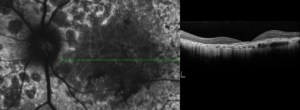

Hyporeflective wedge-shaped band in geographic atrophy secondary to age-related macular degeneration: a little-understood spectral domain optical coherence tomography finding.

Update on Geographic Atrophy in Age-Related Macular Degeneration.